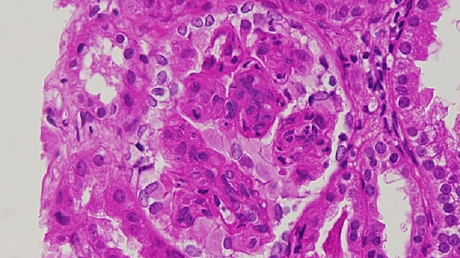

The resected specimen was of 12.5 x 8.5 x 7.5 cm and was submitted for pathological examination. The cut section was grey-white with minimal hemorrhages. Microscopic examination showed round to oval spindle-shaped epitheloid cells with mild pleomorphism embedded in eosinophilic collagenous bands of different thickness as seen in Figure 4.

Cells were arranged in files, cords, nests, vague whorled patterns, and sheets. Scant mitosis was seen without the presence of necrosis. Resection margins were free of infiltration. Immunohistochemistry was positive for vimentin and negative for other markers (SMA, CK, Desmin, CD 34, EMA, CD 45, S100, CD31, HMB45). The pathology examination was consistent with sclerosing epithelioid fibrosarcoma.